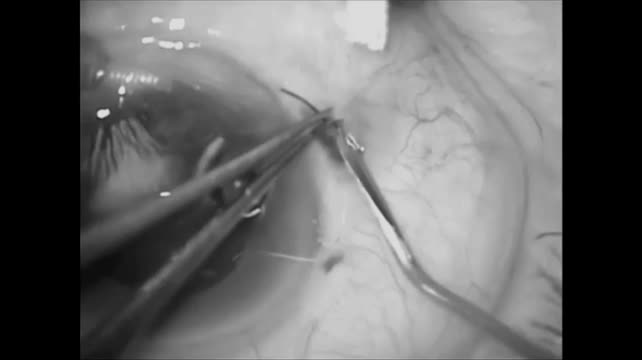

Subluxed Lens

Gabriel Figueiredo, MD